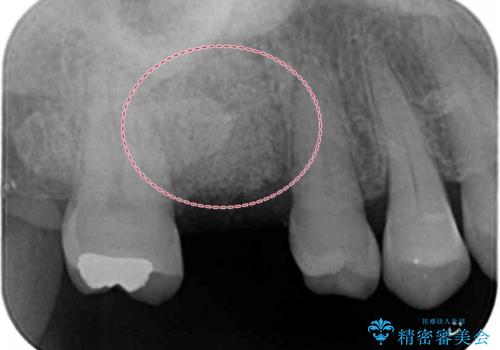

- 症状はないものの、検査の結果右上の奥歯が大きく割れていることが確認されたケースです。

無症状であったため放置していた結果、歯の周囲の骨が溶けてなくなっていました。

歯の深いところまで割れてしまっている場合は健康な状態での歯の保存ができないため抜歯の適応になります。

今回は抜歯後に骨の補填材を足し、適合の良いブリッジを装着していくこととなりました。

抜歯後そのままブリッジを入れるとブリッジと歯茎の間に大きなすき間ができてしまいます。その結果食べ物がつまりやすくなったり、息もれが生じたりと日常生活に支障をきたしてしまうことがあります。

抜歯後に骨を増やしてあげることで、ブリッジと歯茎との間にすき間が生じにくくなり、適合の良いブリッジを入れることが可能となります。